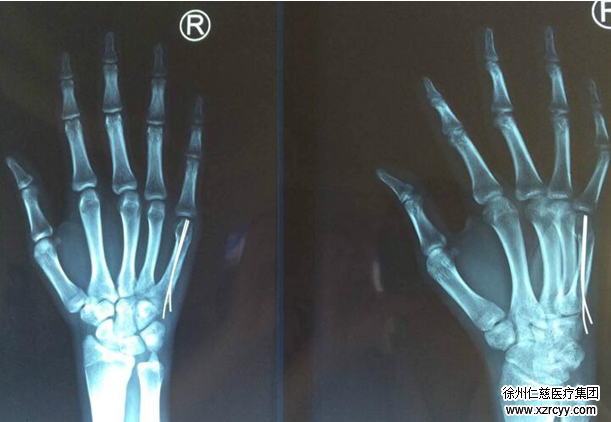

内针固定第五掌骨颈骨折

小东的主治医生betway在线登陆手外二病区齐伟亚主任介绍“传统手术切口大约3公分,而腕关节微创治疗的切口只有0.5公分。术后尺侧前臂石膏功能位固定制动 1 周。然后改为较短的前臂石膏固定,2个月后固定物即可取出。”像小东这样因外力造4、5掌骨骨折的,betway在线登陆运用腕关节微创技术已经成功治疗了数例。